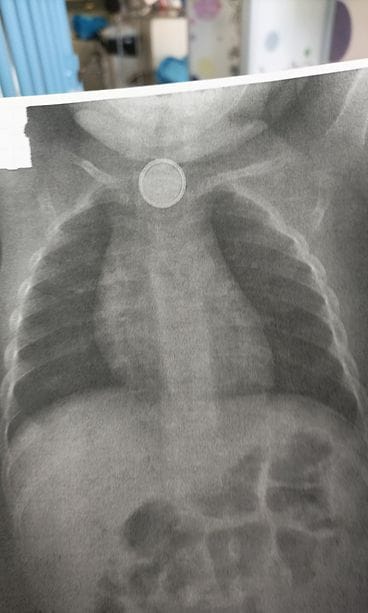

Tapahtumat saivat alkunsa viikko sitten torstaina, kun Valkilan perheen yksivuotias Leo-poika sai käsiinsä kaukosäätimen kolikkopariston.

– Hän kertoi, että säädin oli hetkeä aiemmin ollut pikkuveljen kädessä. Säätimestä puuttui patterin kotelo. Myöskään itse patteria ei löytynyt.

Tässä vaiheessa Hannamari tajusi, että patteri oli Leon nielussa.